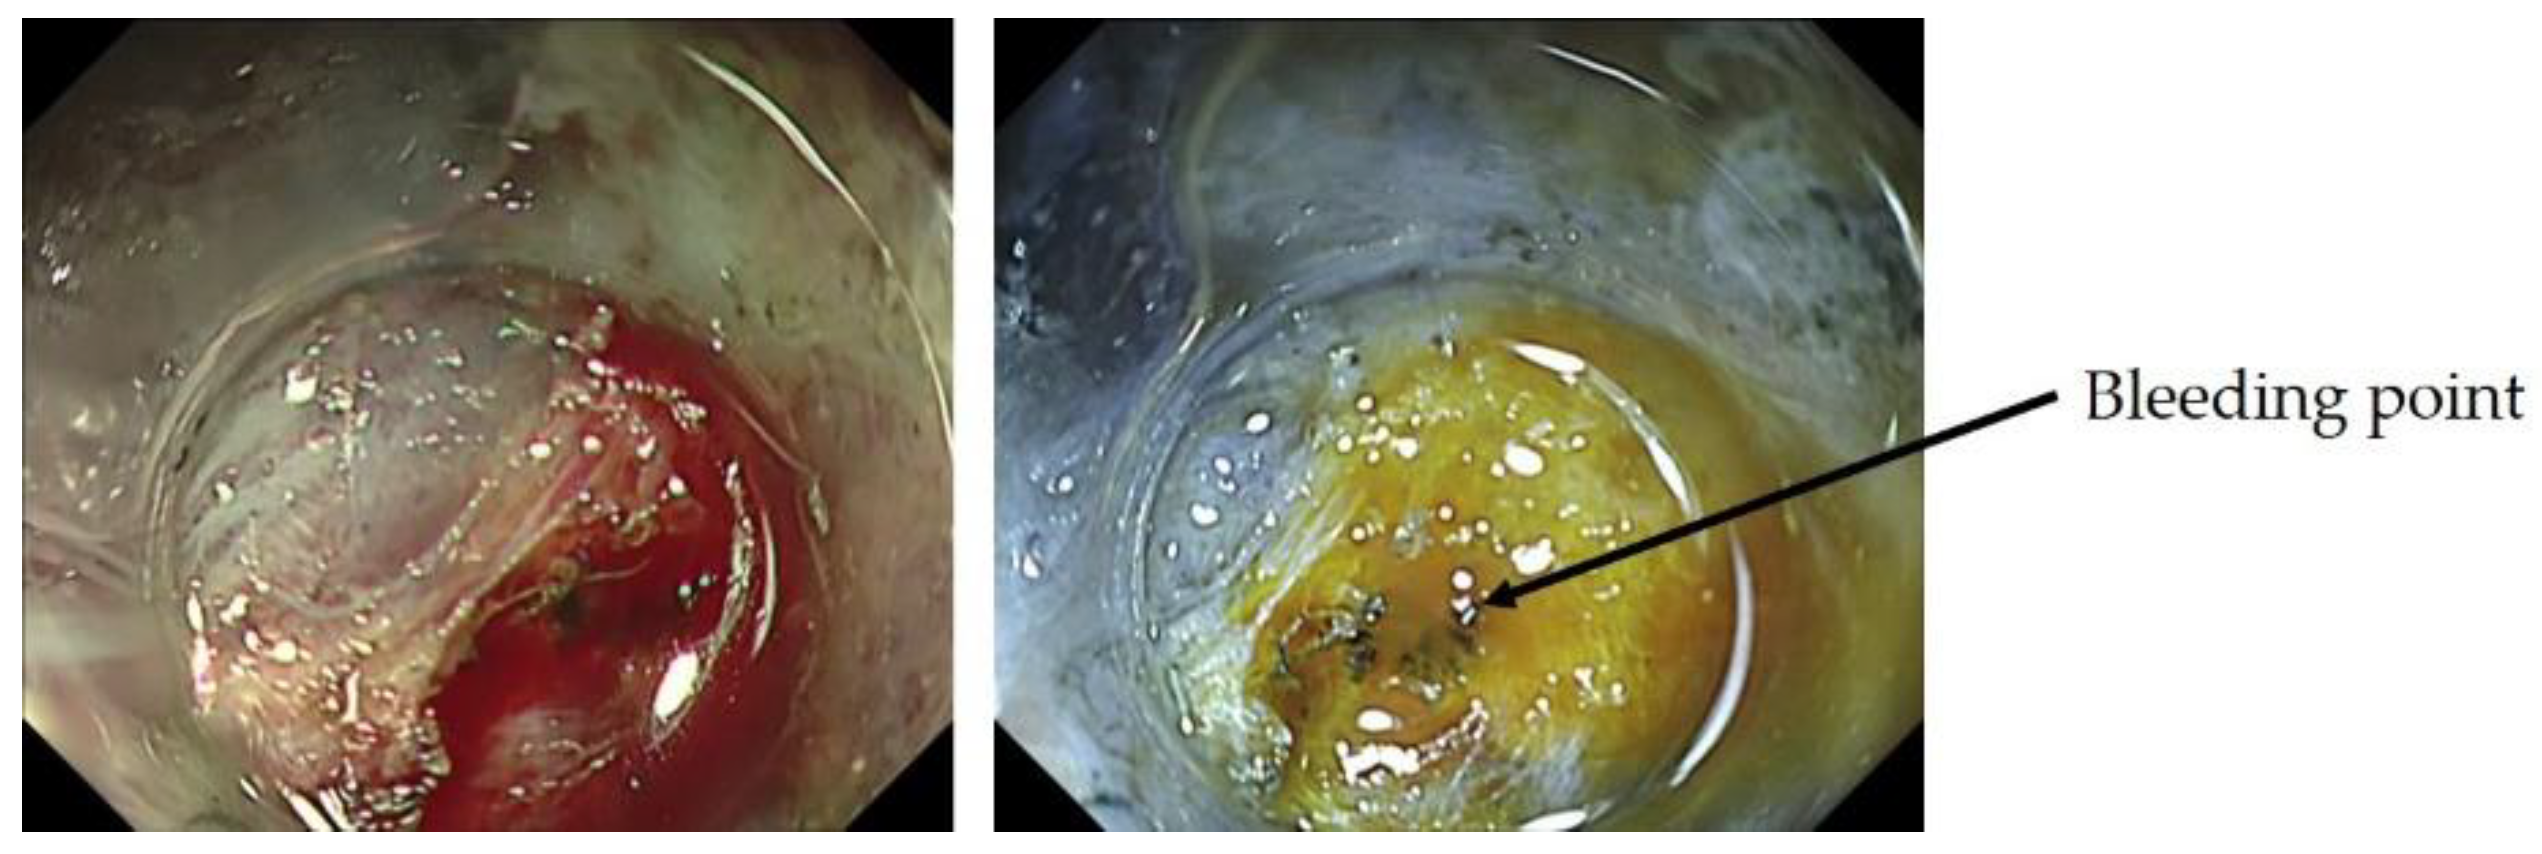

2.4.3. ME-NBI in Determining the Horizontal Extent of Gastric Cancer

- Nonaka, K. Usefulness of the DL in ME with NBI for determining the expanded area of early-stage differentiated gastric carcinoma. World J. Gastrointest. Endosc. 2012, 4, 362. [Google Scholar] [CrossRef]

- Horii, Y.; Dohi, O.; Naito, Y.; Takayama, S.; Ogita, K.; Terasaki, K.; Nakano, T.; Majima, A.; Yoshida, N.; Kamada, K.; et al. Efficacy of Magnifying Narrow Band Imaging for Delineating Horizontal Margins of Early Gastric Cancer. Digestion 2019, 100, 93–99. [Google Scholar] [CrossRef]